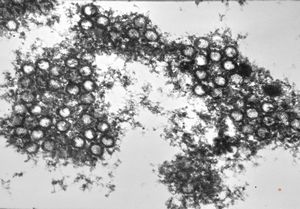

adenovirus in tissue culture - paracrystalline formation